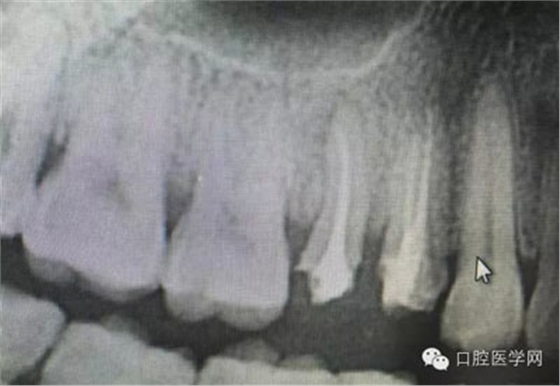

這是一例外院樹脂修復(fù)后十個(gè)月出現(xiàn)牙髓炎癥狀的患者。遇到這樣子的患者大家會(huì)怎么做,證明選擇,還有就是可做可不做治療的如何去平衡。